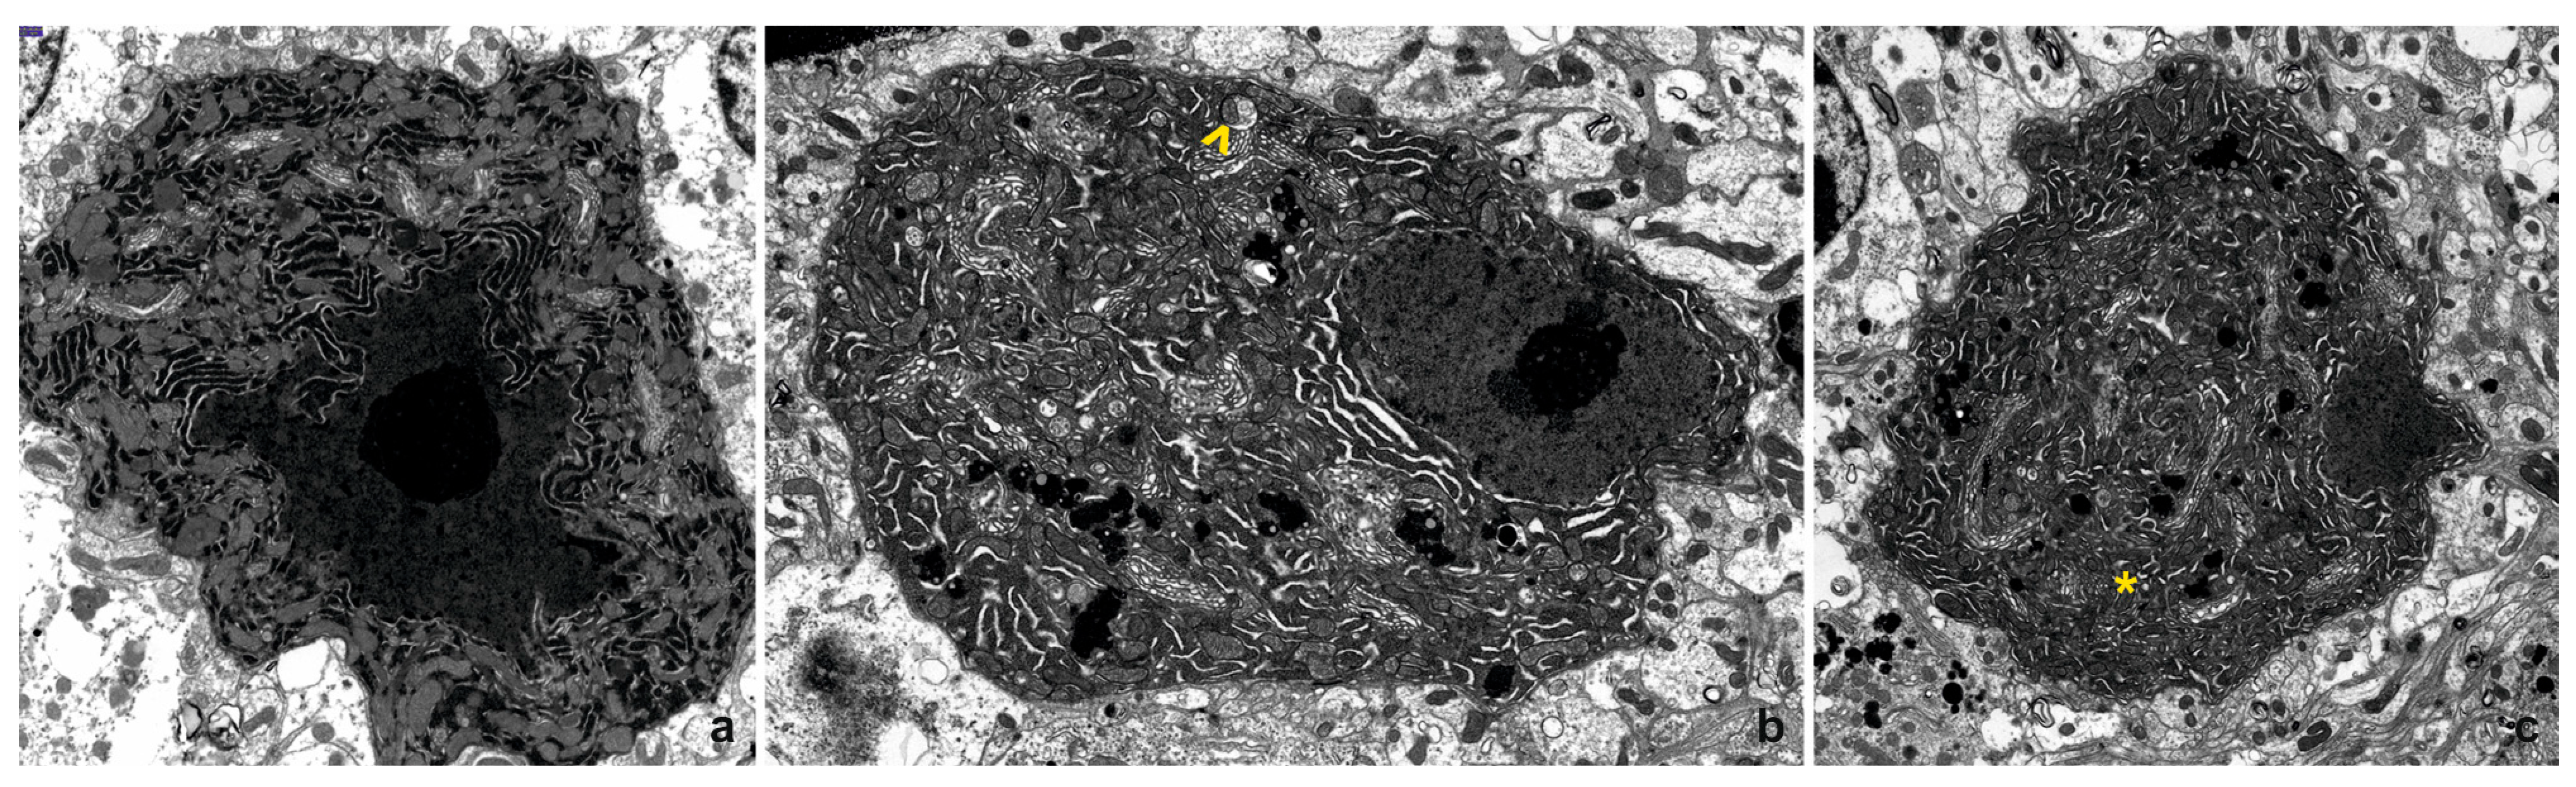

In the 4-month-old WT mice, Purkinje cells exhibit irregular shapes that vary depending on the cross-section, with some displaying a characteristic pear-shaped appearance. The nuclei contain dense chromatin clumps and a prominent nucleolus, while the nuclear membrane frequently forms invaginations, some of which are deep. Mitochondria are typically large, oval, or rod-shaped, with a normal structure characterized by a moderately electron-dense matrix. The Golgi apparatus is well-developed and distributed throughout the cytoplasm, occasionally accompanied by multivesicular bodies. Numerous elongated channels in the rough endoplasmic reticulum (RER) and scattered ribosomes contribute to the cytoplasm’s high electron density (Figure 2a). The cells in the young IL-6KO mice share similar ultrastructural features with those of the young WT mice.

In the 24-month-old WT mice, Purkinje cells show irregular outlines and nuclei that are irregularly shaped, with fewer invaginations compared to younger cells. Chromatin appears more dispersed, while the nucleoli remain large. Mitochondria exhibit varied shapes, some containing slightly translucent matrices or blurred crista structures. Occasionally, individual mitochondria are enclosed by membranes resembling mitophagosomes. The Golgi apparatus is extensive and frequently associated with numerous lysosomes, some containing lipofuscin granules identifiable by their high electron density and distinctive substructure. The cytoplasm remains rich in RER channels and scattered free ribosomes (Figure 2b). In the aged IL-6KO mice, the ultrastructure of Purkinje cells largely resembles that of the aged WT mice. Slightly brightened mitochondria with occasional blurred cristae are present, similar to those observed in aged WT mice. However, fewer lysosomes are observed near the Golgi apparatus compared to what is observed in the aged WT mice (Figure 2c). Despite these differences, the overall cellular architecture remains comparable between the two genotypes in the aged animals.

Figure 2. Representative electron photomicrograph of neurons in the cerebellar cortex: (a) From a 4-month-old WT mouse. Note the irregular shape of the cell nucleus, with dense chromatin and a large, prominent nucleolus (magnification × 7000). (b) From a 24-month-old WT mouse. The cell shows extensive Golgi apparatus cisternae, numerous lysosomes, and lysosomes containing lipofuscin. A mitochondrion surrounded by a membrane and isolated from the cytoplasm is also visible (indicated by ^) (magnification × 4400). (c) From a 24-month-old IL-6KO mouse. A cell with a nucleus exhibiting uneven outlines and regularly dispersed chromatin. Mitochondria of various shapes are visible, with some showing a blurred internal structure (indicated by *) (magnification × 3000).

At the ultrastructural level, electron microscopy provided further insights into the cellular changes occurring in aging Purkinje cells. In the young mice of both genotypes, Purkinje cells displayed well-preserved features, including irregular outlines, prominent nucleoli, and well-developed organelles such as mitochondria and the Golgi apparatus. However, in the aged WT mice, significant degeneration was evident. Purkinje cells exhibited irregular nuclear morphology, blurred mitochondrial cristae, and an increased number of lysosomes containing lipofuscin granules. Similar changes were observed in the aged IL-6KO mice, but these alterations were less pronounced, with fewer lysosomes than the WT animals. Other age-related ultrastructural changes were also observed, including the broadening of the cisterns in the smooth endoplasmic reticulum, which serves as the primary intracellular calcium storage site [35,36]. This broadening suggests disturbances in calcium homeostasis, a critical factor in cellular signaling and metabolism. Degeneration of the Golgi apparatus was another prominent feature, accompanied by the accumulation of dense bodies and vacuoles in the cytoplasm. These changes further disrupted cellular homeostasis, leading to the buildup of lipofuscin granules within the cytoplasm and exacerbating the neurodegenerative process [37]. Together, these alterations illustrate how structural and metabolic disruptions in organelles contribute to the progressive degeneration and eventual loss of Purkinje cells in aging brains. Such structural alterations suggest an attenuation of cellular synthesis and a deficit in trophic support, both hallmarks of aging.